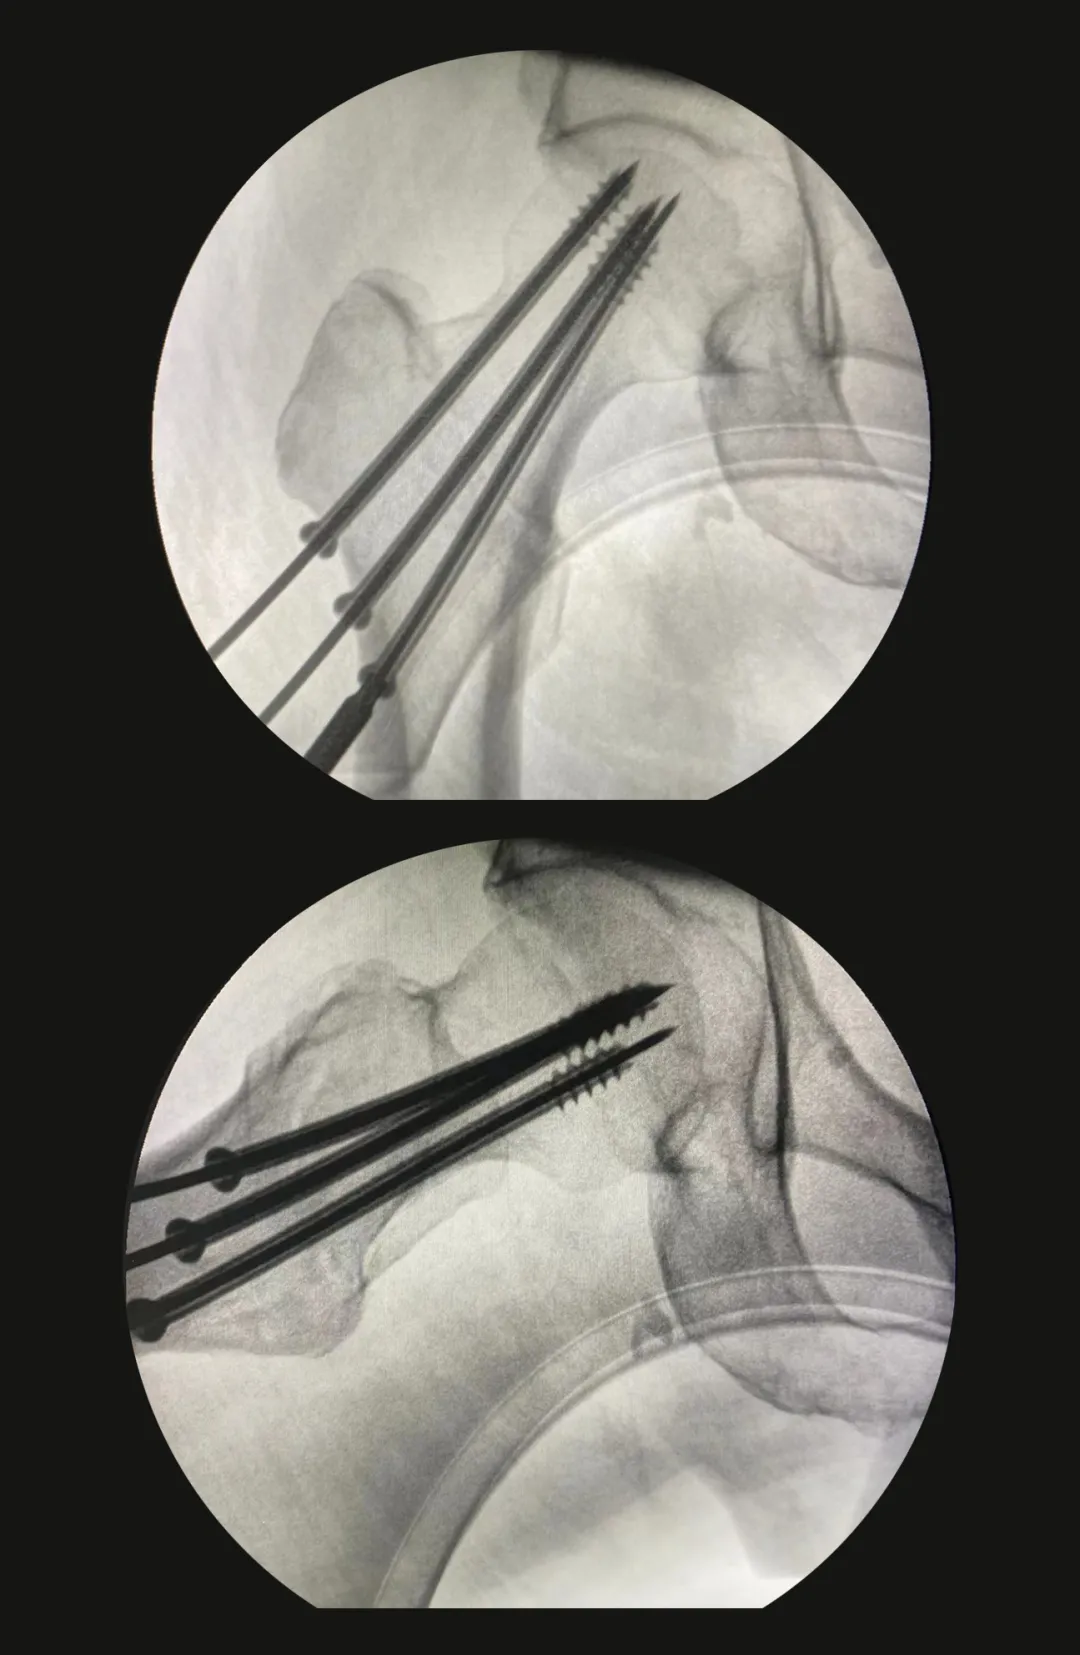

针对老人的受伤情况,我院骨科联合相关科室专家对其进行了会诊,并制定了手术方案。在完成手术前的一系列检查后,12月3日上午,老人被推进了手术室,骨科团队在硬膜外麻醉下为其实施了左股骨粗隆间骨折闭合复位内固定术。

术前 术后

骨科主任表示:手术过程顺利,术中麻醉满意,整个术程仅50分钟,出血约10毫升,术后患者安全返回病房。家属们表示,对手术很满意!